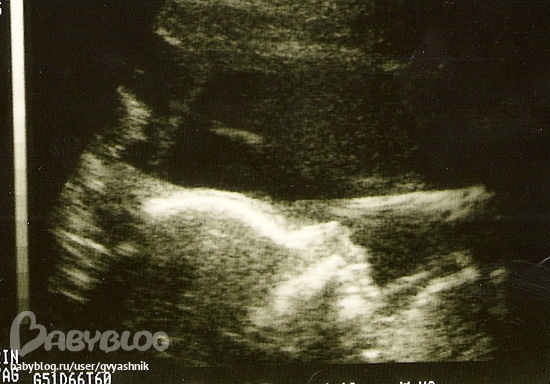

24 недели (не очень понятно отсканировалось, но тут тоже достоинство видно). Лежит полубоком лицом к "публике" и все нараспашку))) На бумажной копии хорошо видно.

Ну там написано Male))) Я там на УЗИ видела, а на фотке сама не могла найти, муж показал) Ну ему виднее)) Там стрелочка есть)) Ножки, тазовые косточки и над ними писюн торчит)) К нему стрелочка. Маленькое все, тк масштаб маленький.